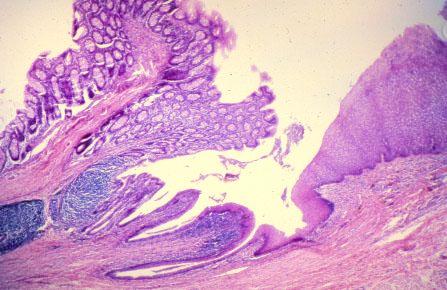

VIII-8, Slide 63, Rectoanal Junction (H&E). The rectum with simple columnar epithelium is on the left, and anal canal with stratified squamous epithelium is on the right.